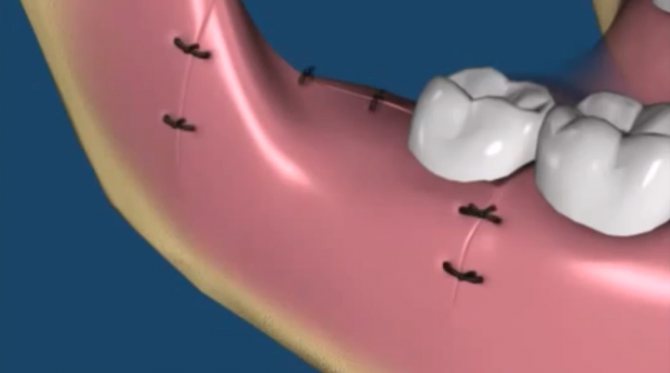

Лунка зуба с одним корнем зарастает быстрее (16-18 суток), чем ранка после удаления многокоренного зуба (19-23 суток). Если рана получилась большой (это происходит после удаления зубов со сложной корневой системой, непрорезавшихся и аномально стоящих зубов), на нее накладывают швы.

- Обработки ротовой полости после удаления: наложение швов (если ранка – рваная или ее края расположены далеко друг от друга) и марлевого тампона, пропитанного кровоостанавливающим средством (его надо удерживать в зубах 20 минут, так как эффективность гемостатического препарата усиливает сдавливание ранки). Не спешите удалять тампон.

- если врач зашил рану, пациенту необходимо прийти в назначенный день для их снятия (в случае наложения саморассасывающихся нитей, швы снимать не требуется).

Как проводится эта методика – если лунка пустая, то под анестезией костные стенки лунки выскабливаются кюретажной ложкой, чтобы создать кровотечение и лунка заполнилась кровью (видео 3). Если же лунка заполнена грануляциями, то их тщательно выскабливают, т.е. делают тот же кюретаж (видео 4). Далее в обоих случаях после того как лунка заполняется кровью – в глубь лунки кладется противовоспалительное лекарство (Альвожель), а на слизистую накладывается несколько швов, чтобы сблизить края раны. Сразу же назначаются антибиотики.

Если операция была сложной, повреждена большая площадь, края десны сильно искромсаны, врач накладывает швы. Они помогут удержать сгусток в альвеоле.

- Зашивание десны. Этот метод используют, когда смыт кровяной сгусток и пациент страдает от симптома «сухой лунки». В таких случаях десна не заживает без медицинского вмешательства. Когда швы наложены, пациенту следует строго соблюдать меры безопасности. Нужно будет промывать и обрабатывать швы антисептическим средством, а также регулярно посещать стоматолога для контроля процесса заживления.